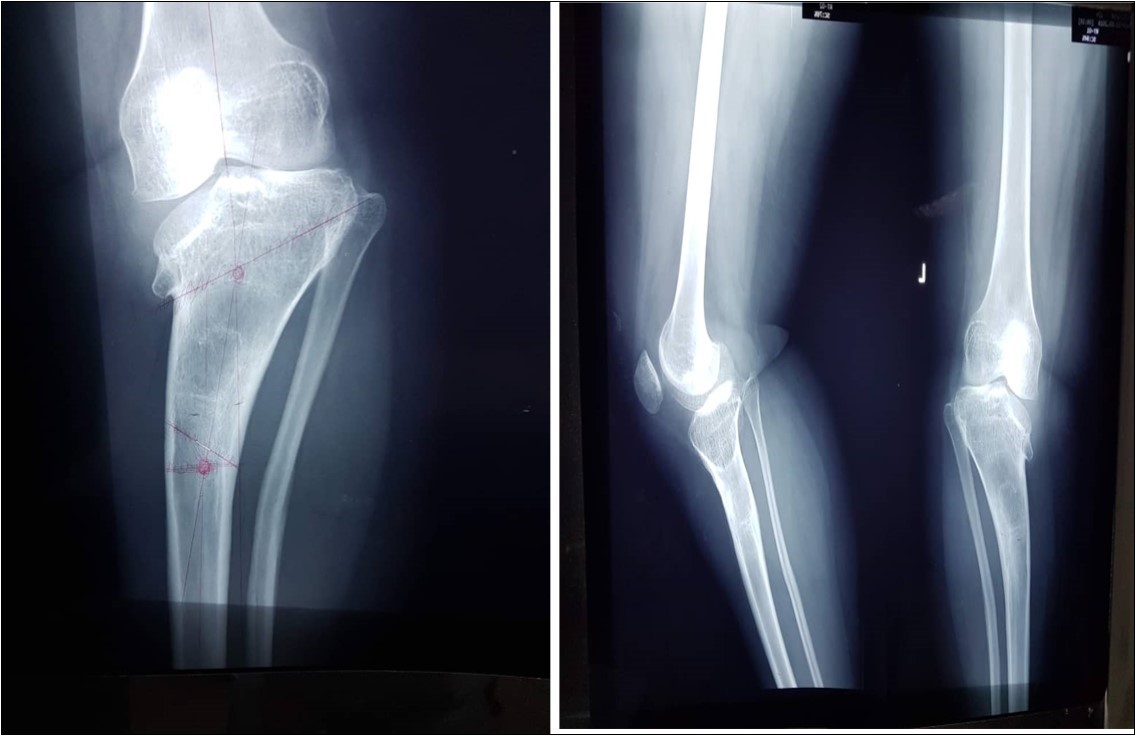

There was a varus angle of 70 degrees as measured by a goniometer when weight-bearing. The range of motion in both knees was 0-100 degrees. X-ray confirmed a Langenskiold stage VI tibia vara on either side, Figure 4.

Figure 4.Fig showing pro-operative radiograph of the left tibia and fibula

Fig showing pro-operative radiograph of the left tibia and fibula